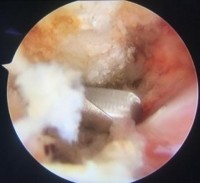

- Dùng đầu mài mài các chồi xương và tạo hình khoang dưới MCV

Hình 2.19. Bộc lộ chồi xương ở góc trước ngoài MCV, mài tạo hình khoang dưới MCV

* Nguồn: ảnh chụp trong mổ của BN Hoàng Lưu Th, mã số bệnh án 08061095